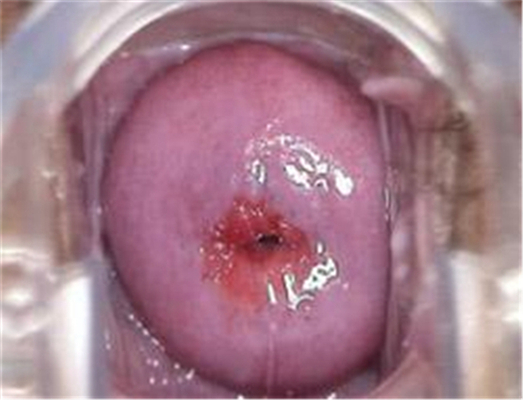

子宮頸炎圖片

宮頸炎